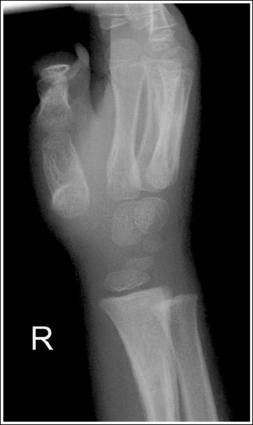

See Figure 4-29 and Box 4-11.

Contrast and density are adequate to demonstrate the scaphoid fat stripe.

• Significance of the scaphoid fat stripe. The scaphoid fat stripe is one of the soft tissue structures that should be visible on all PA wrist projections (Figure 4-30). It is convex and located just lateral to the scaphoid in an uninjured wrist. A change in the convexity of this stripe may indicate to the reviewer the presence of joint effusion or of a radial side fracture of the scaphoid, radial styloid process, or proximal first metacarpal.

The wrist is positioned in a PA projection. The radial and ulnar styloids are at the extreme lateral and medial edges, respectively, of each bone. The radioulnar articulation is open, and superimposition of the metacarpal bases is limited.

• Rotation of the wrist and forearm is controlled by the position of the hand, elbow, and humerus. A PA projection is accomplished by abducting the humerus until it is positioned parallel with the IR and the elbow is in a lateral projection. The hand is then pronated, placing the wrist in a PA projection (Figure 4-31).